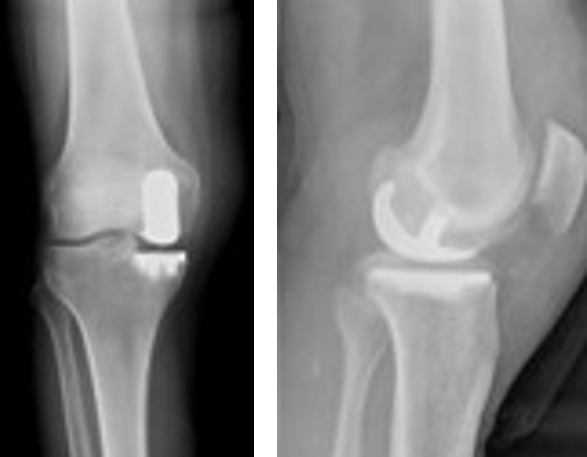

膝関節の一部(内側または外側)を置き換える手術方法であり、人工膝関節全置換術とちがい骨の切除量も半分程度のため侵襲が少なく、回復も早い傾向にあります。ただ適応症例は変形のすくない方、可動域制限がない方、靭帯損傷がない方と全置換術に比較して限られるので、単顆置換術の適応かどうかは医師とご相談ください。

【人工膝関節単顆置換術に用いる人工関節】

【手術後レントゲン】